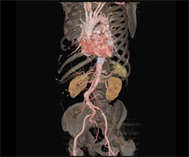

CT画像を用いた3次元画像は今でこそ多くの施設で活用されるようになりましたが、その開発に当放射線科は深く関ってきました。現在では、大動脈瘤や大動脈解離などの大血管疾患や閉塞性動脈硬化症などの末梢血管疾患に加え心臓の冠動脈の3次元画像も提供できるようになり、これまで血管造影でしか得られなかった情報をおよそ10分程度の外来検査で正確に知ることができるようになりました。また、早期脳梗塞の診断において注目されているCT perfusion(CT灌流画像)も海外の大学と共同で開発し国内外での普及に努めてきました。これらの成果は欧州放射線学会から金賞ならびに銀賞を授与され、また日本医学放射線学会でも金賞を受賞し、広く国内外で認められています。

大動脈ステントグラフト